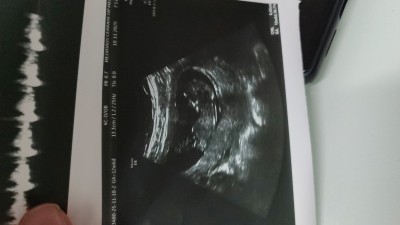

Merhaba ultrason görüntüsü atsam cinsiyet tahmini yaparmısnız

Gebelik haftası 14